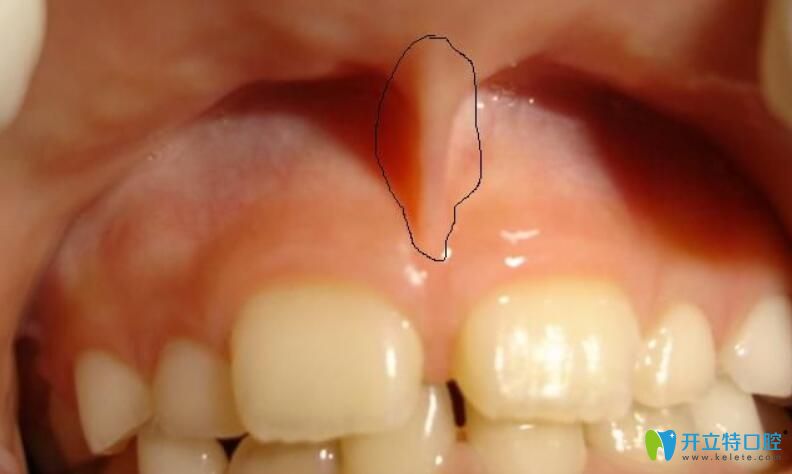

10、多生牙

任何牙位都可能萌生多生牙,不過(guò)多生牙較長(zhǎng)在的位置是上門牙間有多余,多生牙多為畸形牙,它們占據(jù)了正常牙的位置,會(huì)致使這些正常的牙齒出現(xiàn)錯(cuò)位或萌出障礙。

多生牙